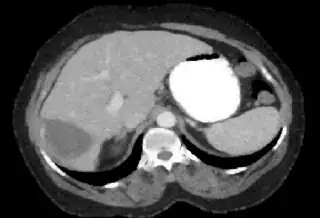

Below I apply two successive morphological openings to the image using a 3x3 circular kernel, and then apply k-means clustering to the gray levels. From your sample images and some I found on the internet, I decided to set k = 4. If you are using high-resolution images, first downsample them to dimensions ~400-600. Otherwise the morphological operation may not have a significant effect, and the k-means will be slow.

Below are some of the opened and segmented images. Of course there's more to be done in terms of

- separating out the liver region

- generalizing this to a large dataset

but hope this is at least a starting point.

You might be able to narrow down the region or interest by filtering out the darkest and the lightest regions from the segmented image. For this, use the k-means cluster centers, check for the extreme values (max and min) and remove the corresponding k values from the labeled image. Then you can look for large structures to the left of the result image. Worst case, you might get a hole on the left side when the extreme region filtering goes wrong. I've updated the code and results.